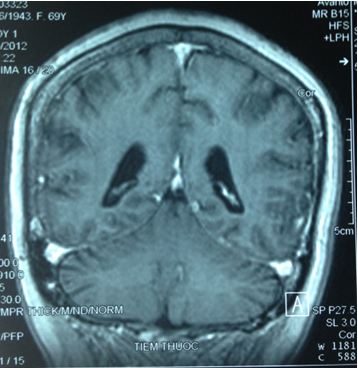

Chụp MRI sọ não (12/12/2011):

Hình 2: Hình ảnh chụp MRI sọ não có khối u não vùng đỉnh trái, 20×19mm, ngấm thuốc quanh u

Chụp MRI sọ não: Sau xạ phẫu 6 tháng bằng dao gamma quay: khối u não tan biến hoàn toàn

Trước điều trị: u não 20×19mm

Sau điều trị 6 tháng: u tan hoàn toàn

Trước điều trị: u 20×19mm

Hình 6: Hình ảnh chụp MRI sọ não sau 6 tháng xạ phẫu bằng dao gamma quay: Khối u não di căn vùng đỉnh trái tan hoàn toàn